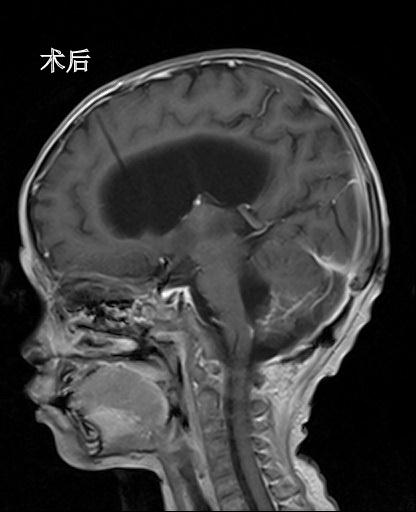

经过脑室外引流术,俊俊的情况开始稳定下来,俊俊的父母看到了生机,在被告知手术风险之后,毅然决定,即便只有百分之一的希望都要进行手术治疗。当所有的临床症状都符合开颅手术的指征后,林坚主任主刀对俊俊开展开颅脑瘤切除手术,第二天上午八点,俊俊被推进了手术室。要把肿瘤和脆弱的脑干以及细小的神经血管精确地剥离开来,并且还要确保不伤到它们,这样的手术极其考验主刀医师的手上功夫和耐力。经过6个多小时连续不断的艰难手术,下午2点多,俊俊被顺利地推出了手术室。

术后MR复查肿瘤基本切除

在对肿瘤进行病理切片分析之后,林坚主任确认俊俊脑瘤是室管膜瘤三级,属于恶性肿瘤,需要进一步放化疗。目前,俊俊病情稳定,恢复良好,准备进入下一阶段的放化疗。